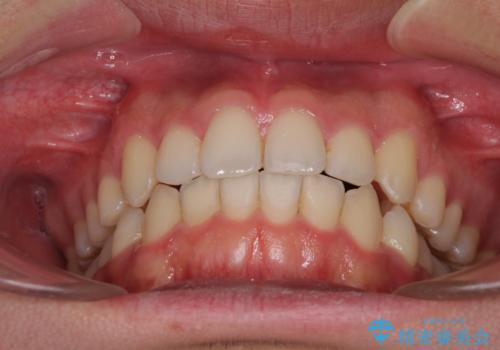

狭い歯列と前歯のデコボコ インビザラインによる矯正治療

- 上下前歯のデコボコを気にして来院された患者様です。

インビザラインによる上下歯列の拡大と、IPR(歯と歯の間を削る)にるスペースの獲得により、前歯のデコボコと狭い歯列を改善することとしました。

比較的軽度な歯列不正であったため、治療期間はそれほど長くはならないと予想されました。

しかしながら、あまりしっかりとマウスピースを装着していなかったため、思いの外期間が長引いてしまいました。

また、仕上がりの歯列にも若干の叢生が残ってしまいました。